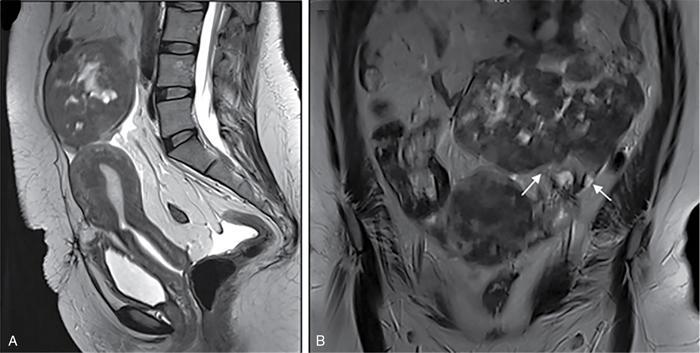

Suriyaprakash Nagarajan, Rupa Renganathan, Suhasini Balasubramaniam, Anupama Chandrasekharan, Kumarsampath Sumeena OVARIAN CYST VERSUS BLADDER Cystic lesions are common in female pelvis and mostly they originate from ovary. Ovarian cysts can arise from epithelial, stromal or germ cell components and can be benign or malignant cystic lesions. Pelvic Ultrasonography (USG) is the preferred imaging modality for evaluation of adnexal cystic lesions. Large simple ovarian cyst appears unilocular, anechoic with thin smooth walls. Such large simple cysts are confused with distended bladder. Distended bladder is a condition in which the urinary bladder is full and the patient is unable to void completely causing abdominal discomfort and pain. Distended bladder can be due to obstruction to passage of urine, neurological disorder or spastic sphincter. Differential diagnosis of cystic lesions in pelvis can be intraperitoneal, extraperitoneal and both intraperitoneal and extraperitoneal. Cystic lesions of intraperitoneal origin includes peritoneal inclusion cyst, paraovarian cyst, mucocele of appendix and hydrosalpinx. It is important to differentiate large simple ovarian cyst and distended bladder when patient presents with lower abdomen pain and the patient’s clinical history helps to make an accurate diagnosis (Table 11.4.1.1). UTERINE VERSUS EXTRAUTERINE MASS Ultrasound is usually the initial imaging modality for the pelvic mass. When USG findings are indeterminate to ascertain the organ of origin and to characterize, the next imaging modality is MRI due to its superior soft tissue resolution and multiplanar imaging capability (Figs. 11.4.2.1 and 11.4.2.2). Signs are demonstrated in Figs. 11.4.2.3 to 11.4.2.6. The sequences used in MRI pelvis are conventional T2WI in all three planes and T1WI in single plane. The problem-solving sequences are oblique coronal and oblique axial T2 along and perpendicular to the long axis of uterus in sagittal localizer. It can identify the organ of origin. Other sequences like T1 fat sat, diffusion-weighted imaging (DWI) and dynamic contrast T1WI with fat sat and subtracted images help to characterize the lesion further. BLADDER MASS VERSUS PROSTATE MASS Irregular mass lesions in the bladder neck are termed as ‘Bladder occupying lesions’. It is often difficult to determine whether the origin of these lesions is the bladder or the prostate gland. Transabdominal Ultrasound with colour Doppler studies and CT imaging do not usually delineate the origin of the lesions. The following features may aid in the differentiation (Table 11.4.3.1): History Painless haematuria Usually asymptomatic Investigations TAS, TRUS, MRI, Cystoscopy-guided biopsy PSA, DRE, TRUS, MRI, TRUS-guided biopsy At what point is the cross over between the two lesions T4 bladder cancer invading the prostate Aggressive prostate cancer protruding into the bladder Epicenter of the lesion Within the bladder Within the prostate gland Central necrosis in the mass Not commonly seen Seen in sarcomas IVU/CT urography Additional lesions in the urinary tract suggest that the bladder occupying mass in the bladder neck is of bladder-origin Prostate masses do not commonly cause masses in the urinary tract except for the very rare metastasis Virtual cystoscopy Additional lesions in the bladder wall and dome suggest that the bladder occupying mass in the bladder neck is of bladder-origin MRI T2 hypointensity Bladder masses are usually T2 hyperintense Seen in adenocarcinomas MRI T2 hyperintensity Bladder masses are usually T2 hyperintense Urothelial tumours infiltrating the prostate, neuroendocrine masses MRI T1 and T2 hyperintensity Bladder masses are usually T1 hypointense and T2 hyperintense Mucinous adenocarcinoma MRS Elevated choline values are seen in highly cellular masses Elevated choline:citrate ratio in prostate malignancies No significant finding in mucinous adenocarcinoma DWI Diffusion restriction is seen in malignant bladder masses No restriction in mucinous adenocarcinoma BPH versus bladder mass Exophytic BPH has signal intensities and appearance similar to and is contiguous with BPH within the gland OVARIAN MASS VERSUS PARAOVARIAN MASS Ultrasonography (USG) is the primary imaging modality in patients presenting with pelvic symptoms. Transvaginal, transabdominal or both should be performed in evaluation of such patients to differentiate ovarian and nonovarian origin of the lesions. Ovarian lesions can be a simple ovarian cyst, complex cyst with septations and solid components or a solid mass. Paraovarian lesions are remnants of the Wolffian duct in the mesosalpinx along fallopian tube or the ovaries and do not arise from the ovary. Paraovarian cysts are classified based on their site of origin into paratubal mesosalpingeal cysts, hydatid cysts of Morgagni, paraovarian cystadenoma and subserosal cysts. Differentiation of ovarian and paraovarian lesion poses significant diagnostic challenge. Both Computed tomography (CT) and Magnetic resonance imaging (MRI) are essential problem-solving tool in determining the site of origin of a pelvic mass. The first step in pelvic mass evaluation is to find out if it is ovarian or nonovarian in origin. Characterization of paraovarian or ovarian lesions is of utmost importance in order to optimize therapeutic procedures and it influences patients management (Figs. 11.4.4.1 and 11.4.4.2). Findings such as ovarian vascular pedicle sign, claw sign, bird beak sign and visualization of normal ovary helps to differentiate between ovarian and paraovarian lesions. Subsequently ovarian lesions should be categorized into benign, indeterminate and malignant masses (Table 11.4.4.1).

Ipsilateral ovary not seen separately from the lesion (Phantom sign) or the cyst is seen to arise from within the ovary (embedded organ sign).

Complete or incomplete septae often seen (Fig. 11.4.1.2A).

Ovarian cysts are anechoic lesions noted on one side of pelvis (Fig. 11.4.1.2B). Normal ovarian stroma can be seen around the cysts in case of small cysts.

Colour Doppler shows vascularity in the septum (Fig. 11.4.1.2C).

Solid components more commonly seen (Fig. 11.4.1.2D).